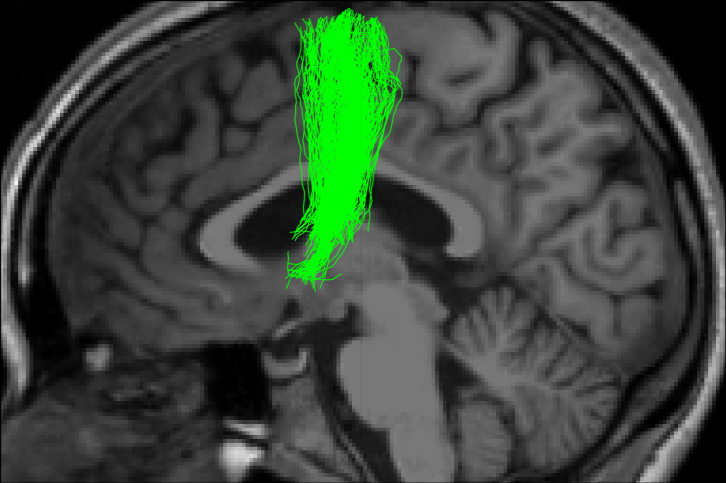

Project: Mariem Boukadi, Simona Brambati et Maxime Descoteaux

Le rôle de la régénération des fibres de matière blanche dans la récupération spontanée du langage dans l’aphasie post-AVC